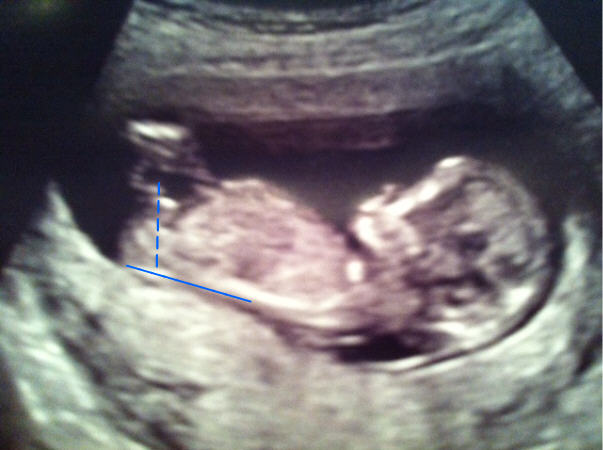

Hi ladies. I am new to the board. I've been looking at all of the recent posts and am not too sure if I know what I am looking for. I had my u/s at 12 weeks 6 days. I think I see a nub. Do you? What do you think, boy or girl? Thanks.

Hmm...there's a little "clutter" around the nub area, but I'm gonna guess GIRL based on the angle of the whitish nub. Any preference for gender?

Great boy nub!

I'm seeing boy!

You're welcome! Sometimes boy nubs can be tricky as people don't always notice the bump on top of the line. Enjoy your baby!